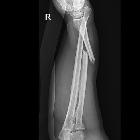

Galeazzi fracture-dislocation

Galeazzi fracture-dislocations consist of fracture of the distal part of the radius with dislocation of distal radioulnar joint and an intact ulna. A Galeazzi-equivalent fracture is a distal radial fracture with a distal ulnar physeal fracture .

Plain radiograph

A forearm series is usually sufficient for diagnosis and management planning. However, good quality orthogonal views are needed to identify and characterize displacement correctly. Features include:

- radial shaft fracture

- commonly at the junction of the middle and distal third

- dislocation of the distal radioulnar joint

- radial shortening may occur, and if greater than 10 mm, suggests complete disruption of the interosseous membrane